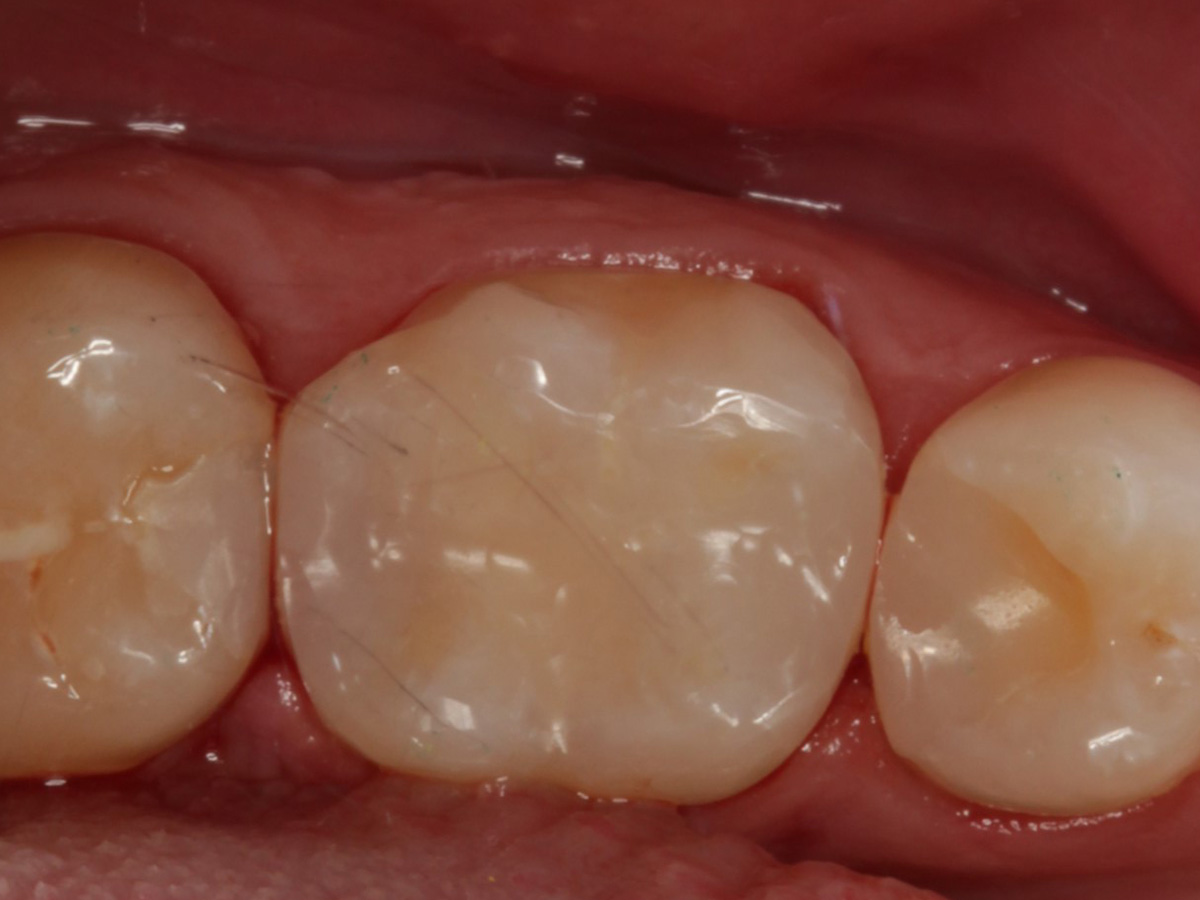

Abbildung 22

Fertige Restauration Zahn 46

Fazit

Also ich kann jetzt für mich sagen, dass die neuen Evolve Matritzen nochmal ein richtiger Schritt nach vorn hinsichtlich Formstabilität, Kantensteifigkeit, und aber insbesondere der Behandlung extrem tiefreichender (approximaler) Defekte sind. Obwohl diese Matrizen angeblich so dick sind wie die Biofit-Matrizen, sind sie gefühlt dünner und dabei gleichzeitig stabiler. Ein Riesenvorteil bei tiefer Zerstörung ist diese zusätzliche "Lasche", mit der fast alle Defekte sauber eingefasst werden können.